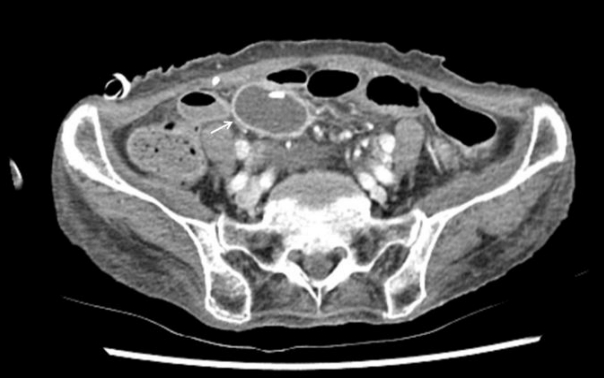

Figure 2.

Abdominal computed tomography showing a 4.7 × 2.8 cm-sized cyst (arrow) with an enhanced wall lying adjacent to the distal tip of the ventriculoperitoneal shunt in the right lower abdomen.

74세 여자가 어지럼증으로 입원하였다. 뇌척수액의 결핵균 핵산증폭 검사에서 양성 소견을 보여 결핵성 수막염으로 진단되었으며 수두증을 동반하여 뇌실복강단락술을 시행하였다. 뇌척수액과 혈액에서 결핵균 외 다른 병원균은 검출되지 않았고, Cryptococcus 항원 검사와 India ink 염색은 음성이었다. 항결핵제 치료를 시작하였고 증세 호전을 보여서 퇴원하였다.뇌실복강단락술 시행 14주 후, 환자는 열감과 구토, 의식저하를 주소로 재입원하였다. 활력 징후는 혈압 120/80 mmHg, 심박수 76회/분, 호흡수 20회/분, 체온 37.7℃였고 의식은 기면 상태였다. 혈액 검사에서 백혈구 10,400/mm3 (중성구 56.1%), 혈색소 11.4 g/dL, 헤마토크리트 33.5%, 혈소판 441,000/mm3였고, 적혈구침강속도는 75 mm/h, 고감도 C-반응단백은 5.83 mg/dL였다. Human immunodeficiency virus 항체와 신속혈장리아긴 검사, Cryptococcus 항원 검사는 음성이었다. 뇌실복강단락을 통한 뇌척수액 검사에서 압력은 120 mmH2O, 백혈구 1.8/uL, 적혈구는 검출되지 않았으며 당 62 mg/dL (혈당 139 mg/dL), 단백질 40.1 mg/dL, 아데노신디아미네이스는 3.0 IU/L였다. 뇌 컴퓨터단층촬영에서 좌측 뇌실의 조영 증가와 주위조직의 부종, 좌측 뇌실내 도관 근위부에서 1.7 × 1.4 cm 크기의 변연부에 조영증강이 되는 낭성병변이 관찰되었다(Fig. 1). 뇌실복강 단락을 통한 복강내 감염의 진행을 확인하기 위하여 복부 조영증강 컴퓨터단층촬영을 시행하여 우하복부에 위치한 도관 말단 부위에서 4.7 × 2.8 cm 크기의 조영증강되는 벽을 지닌 낭종을 확인하였다(Fig. 2). 경험적으로 ceftriaxone 2 g/day와 혐기성균에 의한 혼합 감염의 가능성을 고려하여 metronidazole 1,500 mg/day를 정맥 투여하였고 입원 병일 3일째 뇌척수액 그람 염색에서 효모균이 관찰되어 fluconazole 200 mg/day를 추가로 투여하였다. 입원 병일 7일째 복부의 낭종에 대하여 진단적 복강경 검사를 시행하였다. 복강내 도관 말단은 4 cm 크기의 투명한 액체로 채워진 낭종 안쪽에 위치하고 있었으며 주변으로 유착이 관찰되었다. 낭종과 기존의 뇌실 복강단락을 제거 후 체외 내실 배액관으로 교체하였다. 뇌척수액과 혈액 배양 검사 결과에서 2회 연속으로 Cryptococcus neoformans가 동정되어 Cryptococcus에 의한 뇌막염으로 진단하였고 배양 검사와 핵산증폭 검사에서 결핵균은 동정되지 않아 amphotericin B 0.7 mg/kg/day를 정맥 투여하고 flucytosine 100 mg/kg/day를 경구 투여하였다. 입원 병일 12일째 복부 낭종 흡인액 배양 검사에서 Pseudomonas aeruginosa와 Klebsiella species가 동정되었고 뇌실내 도관 말단 배양 검사에서 Cryptococcus neoformans가 동정되었다. Pseudomonas에 대하여 ciprofloxacin 400 mg/day를 정맥 투여하였다. 입원 병일 19일째 시행한 뇌 컴퓨터단층촬영에서 뇌농양의 크기는 1.2 × 1.0 cm로 감소하였고 수두증은 호전 소견을 보였다(Fig. 3). 입원 병일 21일째부터는 열과 신경학적 증상이 호전되고 의식상태가 명료하여 amphotericin B와 flucytosine을 중단하고 fluconazole 200 mg/day로 교체하였다. 입원 병일 30일째 연속 3번의 뇌척수액 배양 검사에서 음성 소견을 보여서 체외 내실 배액관을 제거하고 새로운 뇌실 복강 단락 도관을 배치하였으며 경구 fluconazole 200 mg/day를 6개월 이상 투약 유지하기로 하고 퇴원하였다. 6개월간의 추적 관찰 기간 동안 환자는 특별한 증세나 재발의 소견 없이 지내는 중이다.